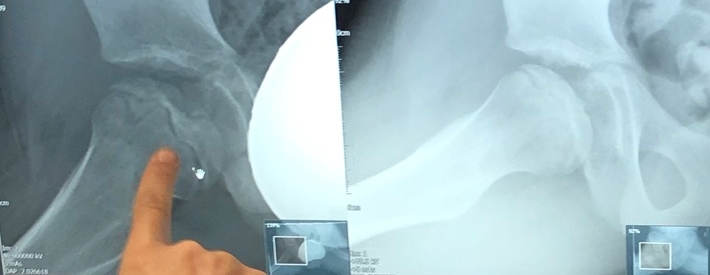

The below scans show his right (bad) hip joint compared to his left (good), and a comparison view of his right hip between Nov 2019 and September 2020. Hard to see with the untrained eye, but combined with what the Consultant tells us, we believe we can see it looking more dense, more rounded, and less black stuff!

September 2020 x-ray showing right (bad) hip compared to left (good) hip.

Comparing November 2019 to September 2020

How it looked November 2017 during the collapse / fragmentation stage